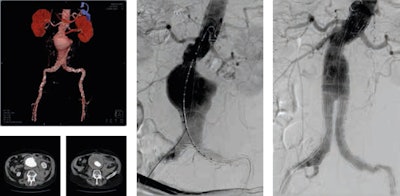

He thinks retroperitoneal hematoma adjacent to an abdominal aortic aneurysm is the most common imaging finding indicative of aneurysm rupture. Endovascular aneurysm repair (EVAR) has become an established technique for the treatment of many infrarenal aortic aneurysms. Less invasive than open surgical repair, EVAR is associated with better outcomes, according to Pyra (see figures 1 and 2).

The interventional radiologist's remit also rests on the repair of other relatively common pathologies; acute aortic dissection, for example, occurs when blood enters the medial layer of the aortic wall through a tear or penetrating ulcer in the intima and tracks along the media, forming a second blood-filled channel within the wall.

"It is the interventional radiologist's task to identify and dilate the true lumen, exclude the entry tear by implanting a stent graft and, if necessary, provide blood inflow to the vital abdominal organs," he said.